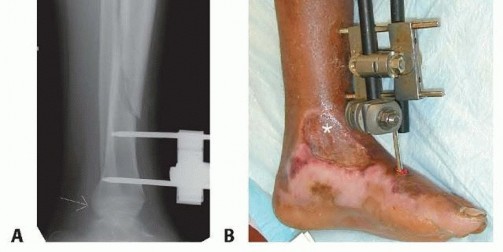

The fracture is then manually reduced, using the pins for traction if necessary, and the frame is connected (

TECH FIG 1A

).

In cases of soft tissue injury requiring the ankle to be immobilized, extending the frame to the first or fifth metatarsal can allow easier wound management (

TECH FIG 1B

The pin sites are covered with iodine-soaked gauze.

TECH FIG 1

•

A.

External fixation in a patient with a compartment syndrome.

Arrows

mark the proximal and distal growth plates. The proximal pins start fairly distally to avoid the tubercle physis.

B.

In this patient, an external fixator was used for a grade 2 open fracture treated with delayed closure. The patient also had a degloving injury requiring a flap and skin graft over the medial ankle. The frame was extended to the first metatarsal to immobilize the foot during healing. Although somewhat bulky, the “double stack” configuration of the frame allows for easy dynamization.